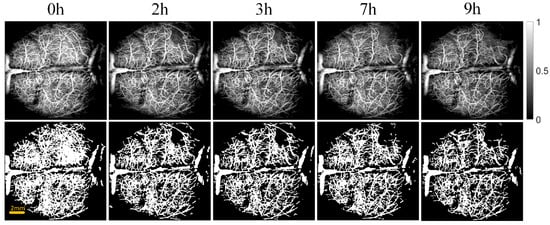

2.2.3. Blood Vessels Segmentation

2.2.4. Quantification of Vascular Parameters

2.2.5. OCT Attenuation Imaging

2.2.6. Quantization of Edema Parameters